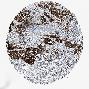

LUNG ADENOCARCINOMA (VALIDATION) - Interactive survival scatter ploti

The Survival Scatter plot shows the clinical status (i.e. dead or alive) for all individuals in the patient cohort, based on the same data that underlies the corresponding Kaplan-Meier plots. Patients that are alive at last time for follow-up are shown in blue and patients who have died during the study are shown in red.

The x-axis shows the expression levels (FPKM) of the investigated gene in the tumor tissue at the time of diagnosis. The y-axis shows the follow-up time after diagnosis (years). Both axes are complimented with kernel density curves demonstrating the data density over the axes. The top density plot shows the expression levels (FPKM) distribution among dead (red) and alive patients (blue). The right density plot shows the data density of the survived years of dead patients with high and low expression levels respectively, stratified using the cutoff indicated by the vertical dashed line through the Survival Scatter plot. This cutoff is automatically defined based on the FPKM cutoff that minimizes the p-score. The cutoff can be changed by dragging the vertical line or by entering a cutoff value in the square labeled "Current cut-off".

Under the Survival Scatter plot the p-score landscape (black curve; left axis) is shown together with dead median separation (red curve; right axis). Dead median separation is the difference in median mRNA expression between patients who have died with high and low expression, respectively. It is calculated as follows: median FPKM expression of dead patients with high expression - median FPKM expression of dead patients with low expression. This is intended to aid the user in visually exploring custom cutoffs and the associated p-scores and dead median separation.

Individual patient data is displayed and can be filtered by clicking on one or more of the category buttons on the top of the page. Categories describing expression level and patient information include: high, low, alive, dead, female, male and tumor stages. The scale of the x-axis can be toggled between linear and log-scale by clicking on the "x log" button. Mouse-over function shows TCGA ID, patient information and mRNA expression (FPKM) for each patient.

& Survival analysisi

Kaplan-Meier plots summarize results from analysis of correlation between mRNA expression level and patient survival. Patients were divided based on level of expression into one of the two groups "low" (under cut off) or "high" (over cut off). X-axis shows time for survival (years) and y-axis shows the probability of survival, where 1.0 corresponds to 100 percent.

LMLN is not prognostic in Lung Adenocarcinoma (validation)

Best expression cut offi

Based on the FPKM value of each gene, patients were classified into two groups and association between prognosis (survival) and gene expression (FPKM) was examined. The best expression cut-off refers the FPKM value that yields maximal difference with regard to survival between the two groups at the lowest log-rank P-value. Best expression cut-off was selected based on survival analysis .

When clicking on this number, the vertical dashed line indicating cut-off, the interactive survival plot, and the Kaplan-Meier curve will be adjusted to show results based on the best expression cut-off.

: 3.77

Median expressioni

Median expression refers to the median FPKM value calculated based on the gene expression (FPKM) data from all patients in this dataset. When clicking on this number, the vertical dashed line indicating cut-off, the interactive survival plot, and the Kaplan-Meier curve will be adjusted to show results based on the median expression.

: N/A

P scorei

Log-rank P value for Kaplan-Meier plot showing results from analysis of correlation between mRNA expression level and patient survival.

N/A

Average pTPM 6.1

Number of samples 105